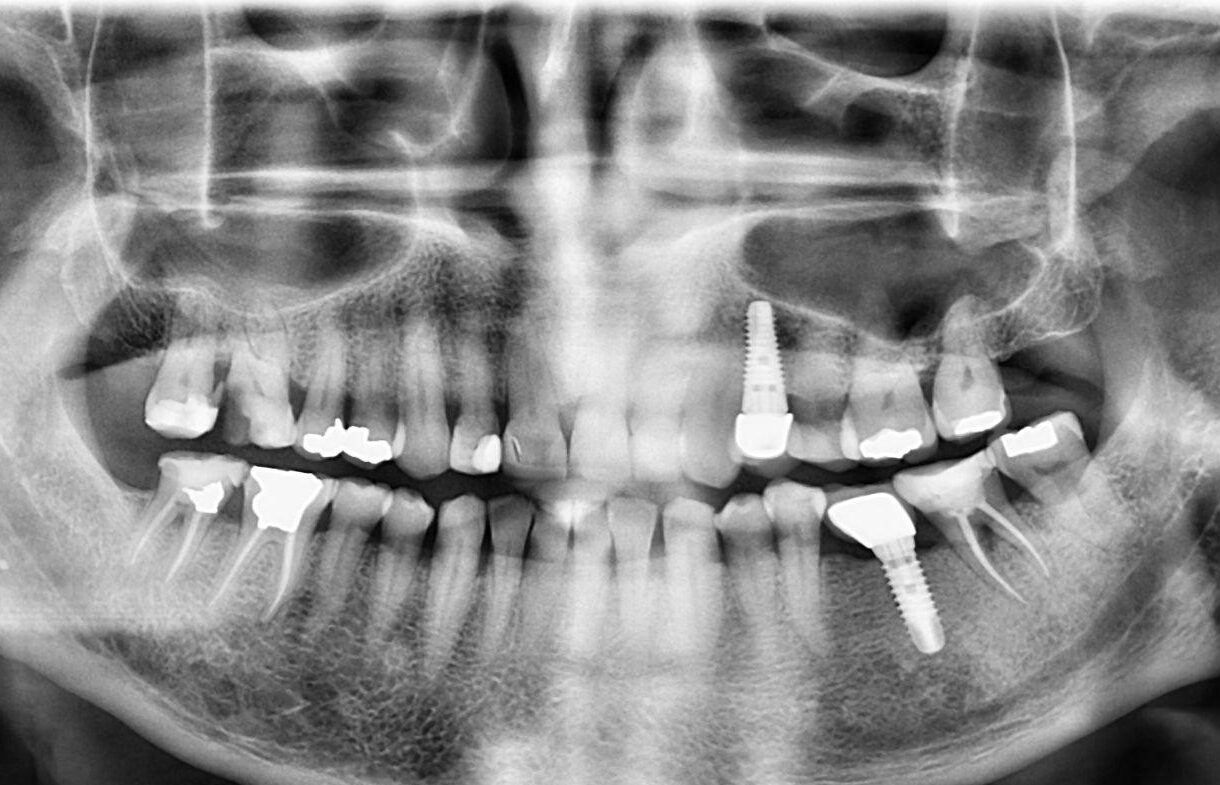

4. What option can be selected for upper jaw of this panoramic X ray?

5 / 23